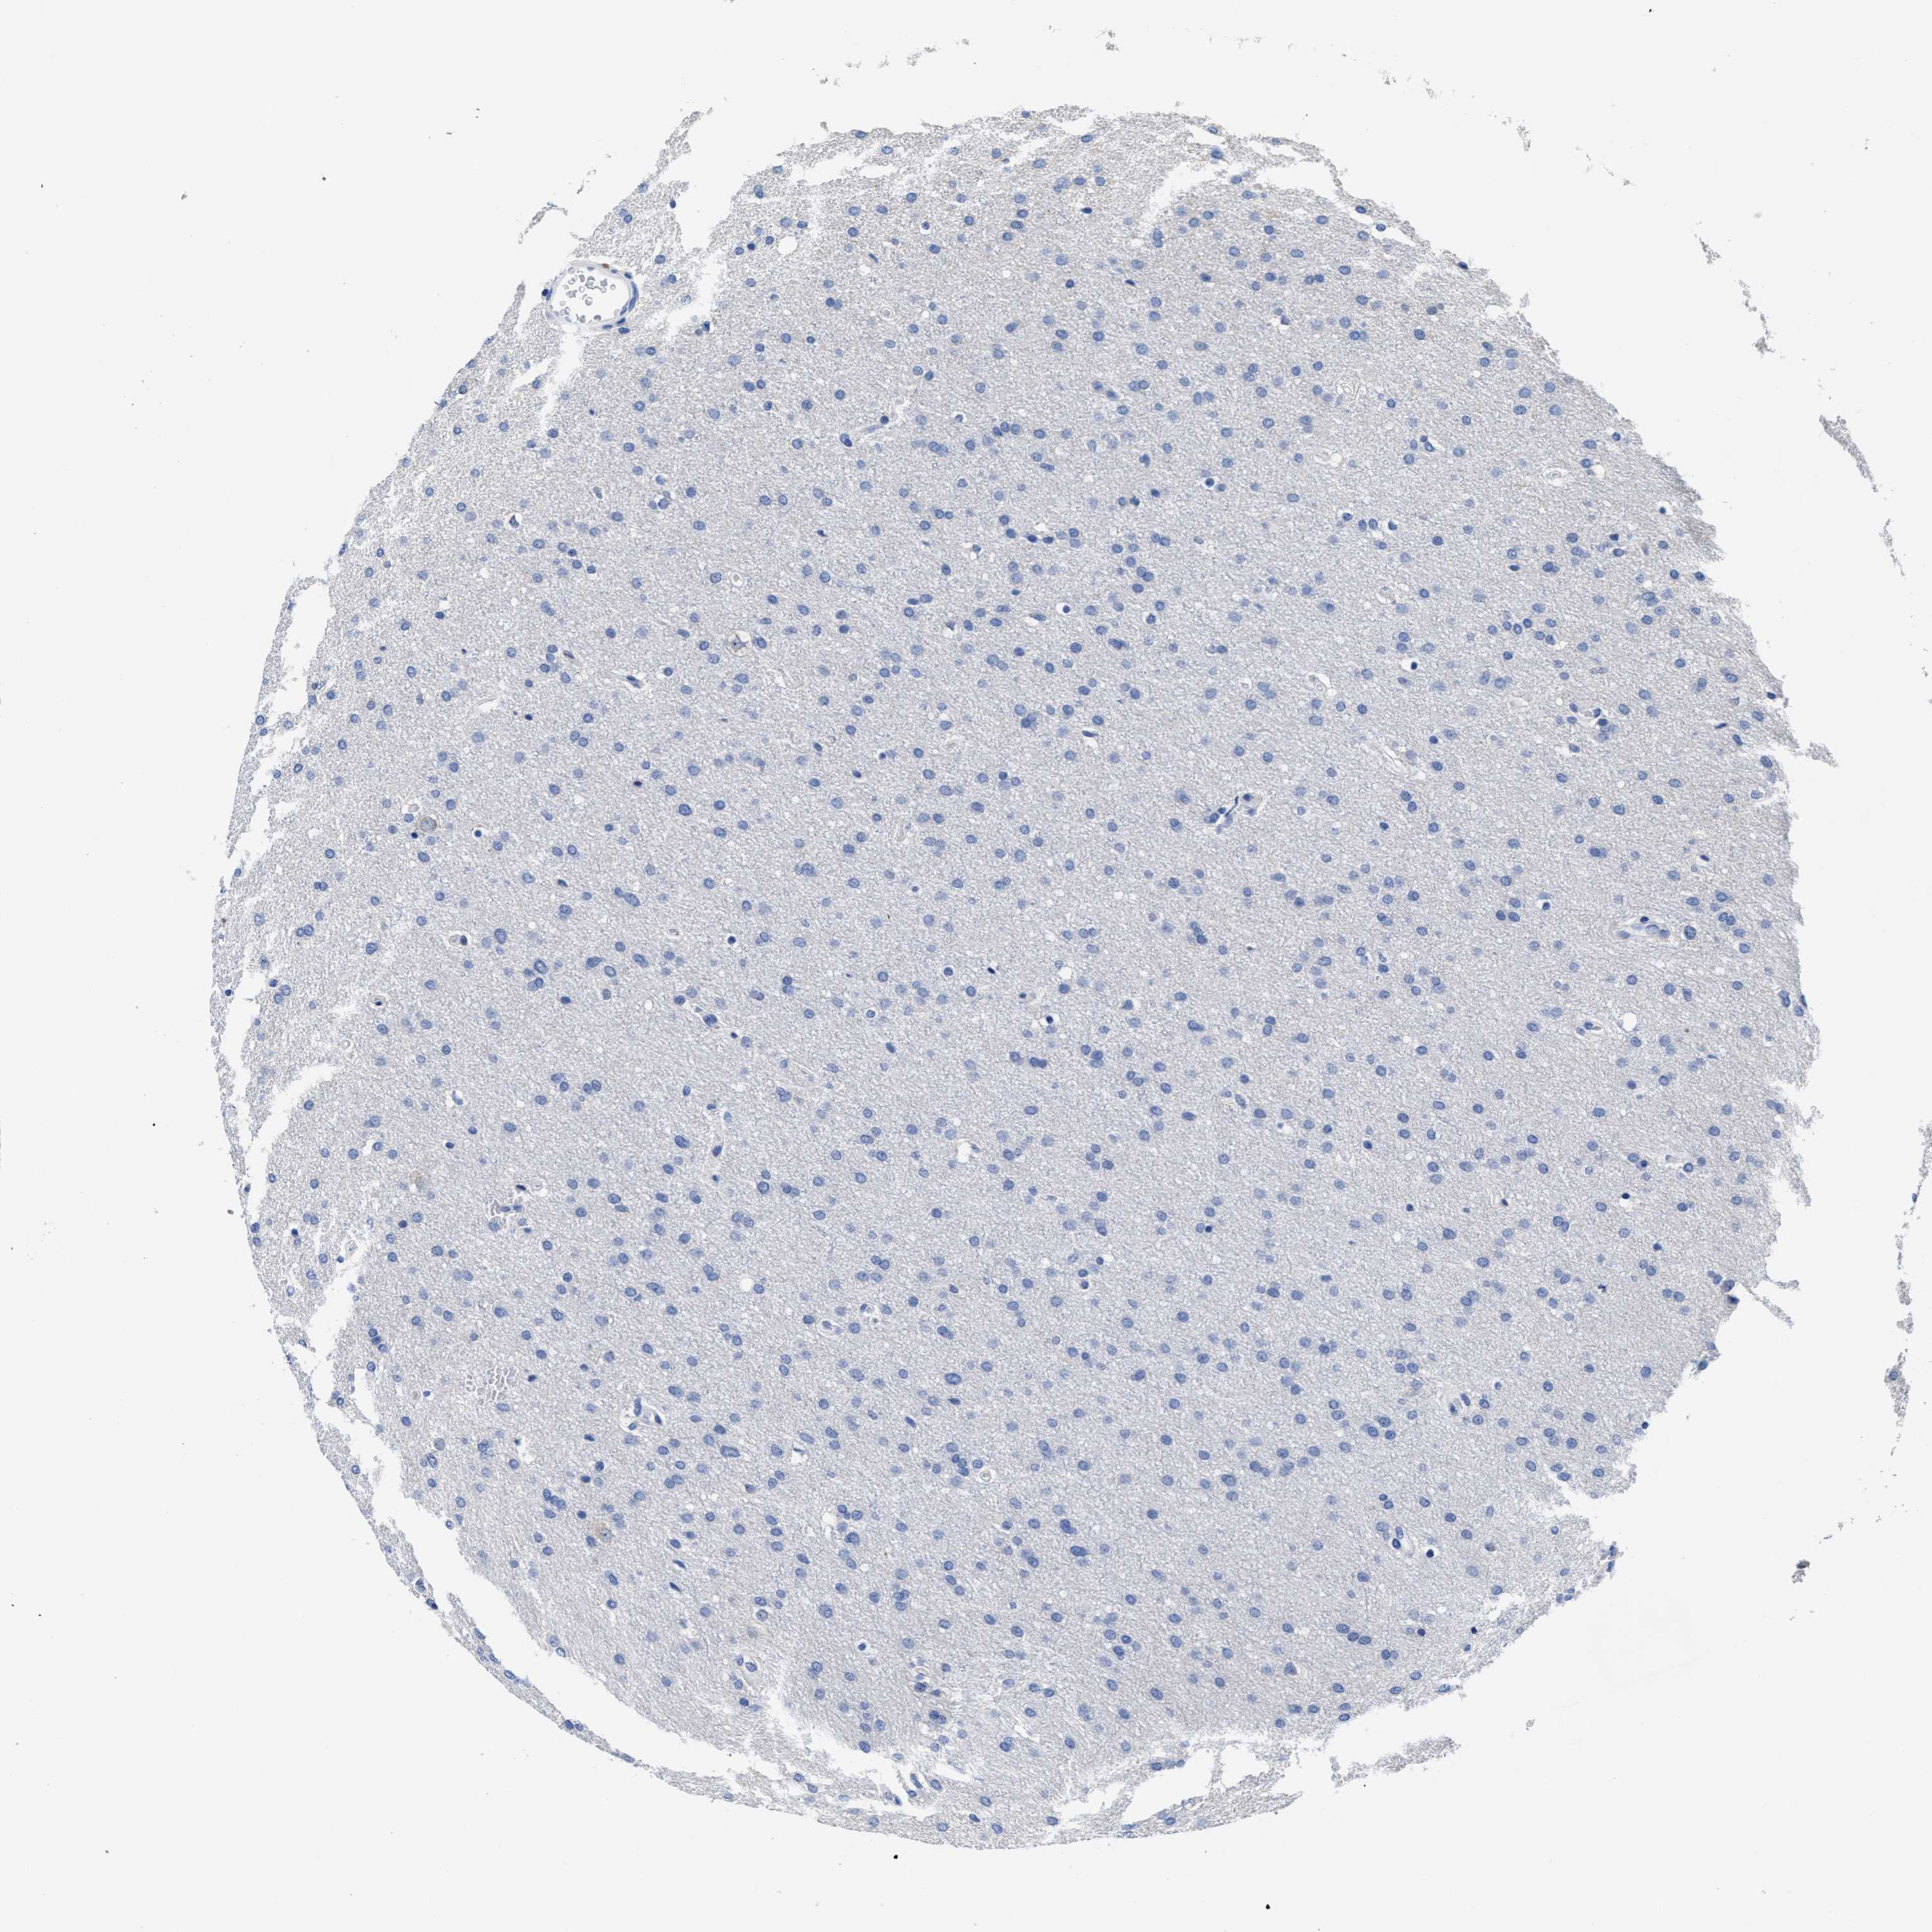

GLIOMA - Protein expressioni

A mouse-over function shows sample information and annotation data. Click on an image to view it in a full screen mode. Samples can be filtered based on level of antibody staining by selecting one or several of the following categories: high, medium, low and not detected. The assay and annotation is described here.

Note that samples used for immunohistochemistry by the Human Protein Atlas do not correspond to samples in the TCGA dataset.

Antibody stainingi

Antibody staining in the annotated cell types in the current human tissue is reported as not detected, low, medium, or high, based on conventional immunohistochemistry profiling in selected tissues. This score is based on the combination of the staining intensity and fraction of stained cells.

Each image is clickable and will lead to virtual microscopy that enables deeper exploration of all samples and also displays staining intensity scores, fraction scores and subcellular localization as well as patient and tissue information for each sample.

Antibody HPA018537

Antibody HPA018820

Staining

High

Medium

Low

Not detected

Intensity

Strong

Moderate

Weak

Negative

Quantity

>75%

75%-25%

<25%

None

Location

Nuclear

Cytoplasmic/membranous

Cytoplasmic/membranous,nuclear

Glioma, malignant, High grade

Glioma, malignant, Low grade